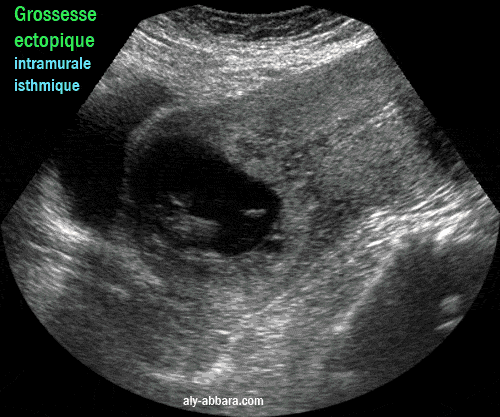

• Images d'IRM montrant une grossesse ectopique évolutive de 10,5 SA, localisée dans la paroi antérieure de la région isthmique de l'utérus ; il s'agit d'une localisation rare de la grossesse ectopique (grossesse extra-utérine intramurale isthmique) pouvant être expliquée par la présence d'un diverticule (ou une béance) dans l'ancienne cicatrice d'une césarienne permettant la nidation de la grossesse dans cette zone de la paroi utérine.

• À l'échographie, on met en évidence de la présence d'un sac gestationnel de 60 x 70 mm, avec un fœtus vivant de 44 mm de longueur crânio-caudale (10 semaines d'aménorrhée et 5 Jour).

Ce sac gestationnel n'est pas localisé dans la cavité utérine, car il s'est développé dans la paroi antérieure de la région isthmique de l'utérus, avec une évolution, en particulier antérieure, vers la paroi postérieure de la vessie, mais heureusement, il reste séparé d'elle par une fine couche myométriale qui ne dépasse pas les 2 mm d'épaisseur.

• Ces données échographiques ont été confirmées par l'IRM qui permet de mettre en évidence les rapports anatomiques de cette grossesse avec les organes avoisinants et qui prouve l'intégrité de la paroi vésicale postérieure.